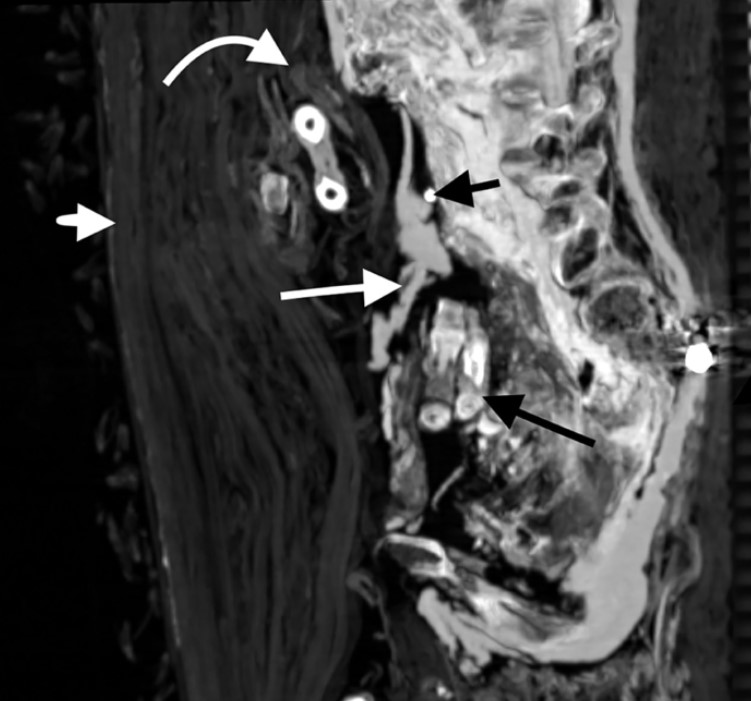

Dưới tấm vải lanh quấn xuyên suốt từ đầu đến chân của xác ướp, công việc của những người ướp xác đã hiển lộ rõ ràng. Một vết rạch dọc dài 9 cm đã được thực hiện tại vùng dưới sườn trái của [pharaoh] Amenhotep I cho thấy thủ thuật loại bỏ các cơ quan nội tạng; khoang bụng dưới chứa đầy vải lanh đã qua xử lý bằng nhựa cây. Tuy nhiên, trái tim đã không được lấy ra ngoài, bộ não cũng đã được phát hiện vẫn còn nguyên vẹn và nằm ở phía sau hộp sọ.

Vị vua bên trong xác ướp

Các ước tính trước đây về tuổi của [pharaoh] Amenhotep I được thực hiện dựa trên phương pháp khám nghiệm bằng X-quang lần đầu tiên vào năm 1932 đã phát hiện ông [băng hà] trong khoảng từ 40 đến 50 tuổi. Sau đó vào năm 1967, bằng phương pháp phân tích răng, [các nhà khoa học đã định ra] ông qua đời ở năm 25 tuổi. Tuy nhiên, trong các lần chụp CT gần đây, [các nhà khoa học đã] quan sát tại phần khớp dính xương mu (phần xương ở phần xương chậu dưới trở nên nhẵn dần theo tuổi tác), đã định ra rằng ông qua đời ở tuổi 35.